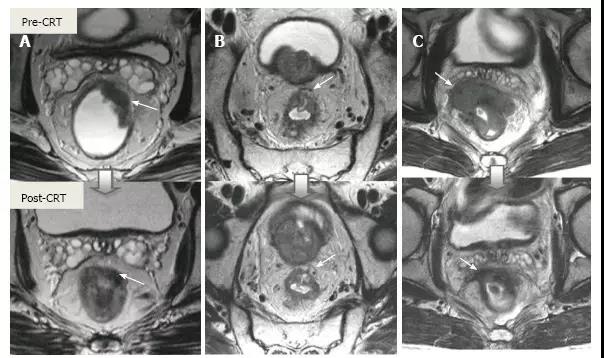

2.直肠系膜筋膜距离

如果在 CRT 后距离 MRF 至少 1 毫米观察无肿瘤边缘则认为 CRM 未累及,阴性预测值达 98%,但阳性预测值很低。有些直肠癌,CRT 导致肿瘤容积明显减少同时,也导致最初与 MRF 相接的缘收缩,此时难以确定此区域是否存在肿瘤细胞(图 22 和 图 23)。

图 23. 放化疗对直肠肿瘤和周围切缘的影响。不同病人的 T2 加权轴位磁共振图像(上:基线,下:CRT 后)。A. 在没有 MRF 侵袭的 ypT2 直肠肿瘤中,在直肠系膜筋膜(箭头)处厚厚的低信号组织浸润导致过度分期;B. 在没有 MRF 侵袭的 ypT3 直肠肿瘤中,肿瘤的纤维性纤维性缩小,CRM 阳性可疑(箭头);C. 直肠肿块明显缩小,低信号强度浸润直肠系膜筋膜(箭头)。手术中证实肿瘤侵犯了直肠系膜筋膜。